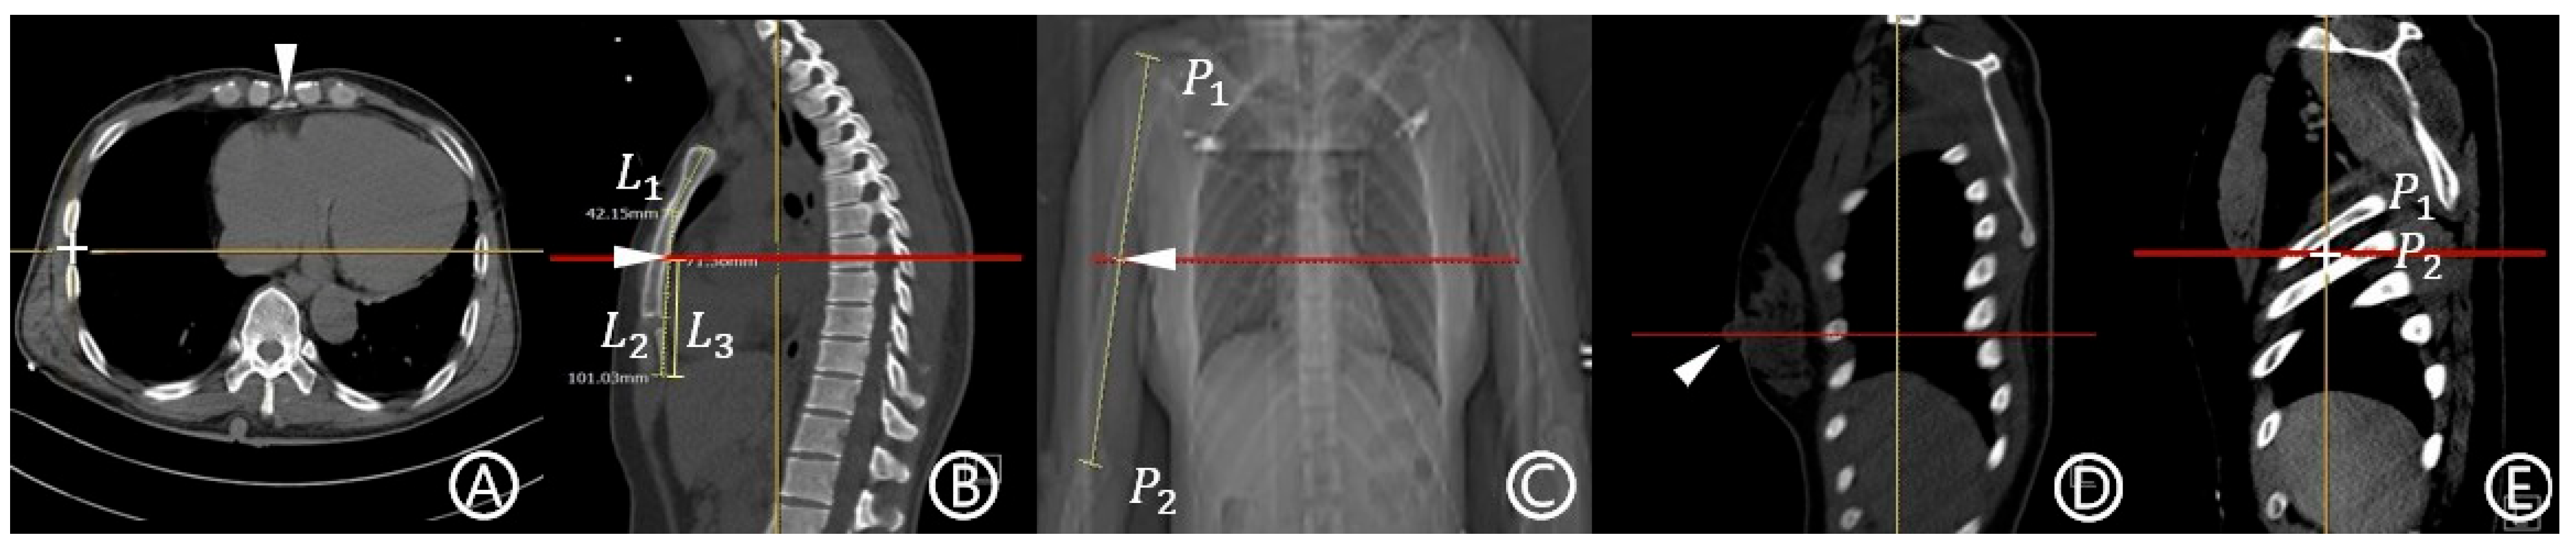

- MAL: This term was defined as in our previous study based on the work of Wax and Leibowitz [14,15]. On the axial CT image at the level of the xiphoid process, the peripheral point of the pleura was designated as the reference point (Figure 1A). A craniocaudal line drawn from this point was considered the MAL.

- Fifth ICS: The term was defined as the space between the fifth and sixth ribs, identified on the sagittal image (Figure 1E)

- Methods and possible insertion sites used in this study: For each anatomical point described above, the corresponding level on the axial plane was identified. The point at which this level intersected the MAL was defined as the possible insertion site. Each method was named according to its anatomical reference point: mid-sternum, mid-arm point, nipple, and fifth ICS methods.

- Possible insertion route: The term was defined as a horizontal scout line passing through each possible insertion site.

- Eligibility for insertion within the safe triangle (safety zone): A possible insertion route was considered eligible if it did not intersect the pectoralis major and latissimus dorsi, and it is positioned superior to the fifth ICS level.